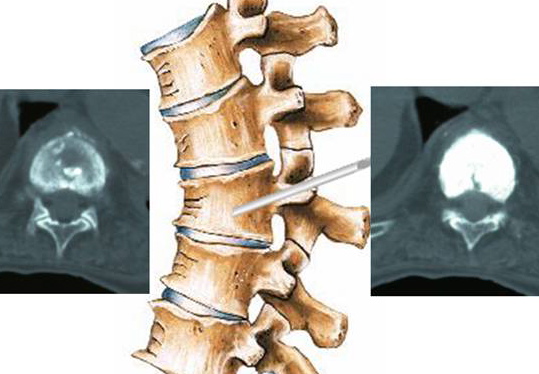

Cimentoplastie Vertebrale Et Cyphoplastie Espace Francilien Du Rachis

visitez l'article complet ici : https://rachis.paris/chirurgie-du-rachis/rachis-lombaire/cimentoplastie-vertebrale-cyphoplastie/

.localisations vertébroplastie injection de ciment acrylique dans le corps vertébral vert moins autant de vertébroplasties faites •de nombreuses études faites dans le depuis 2005 10 patients par an •environ 1500 vertèbres traitées dans le service.